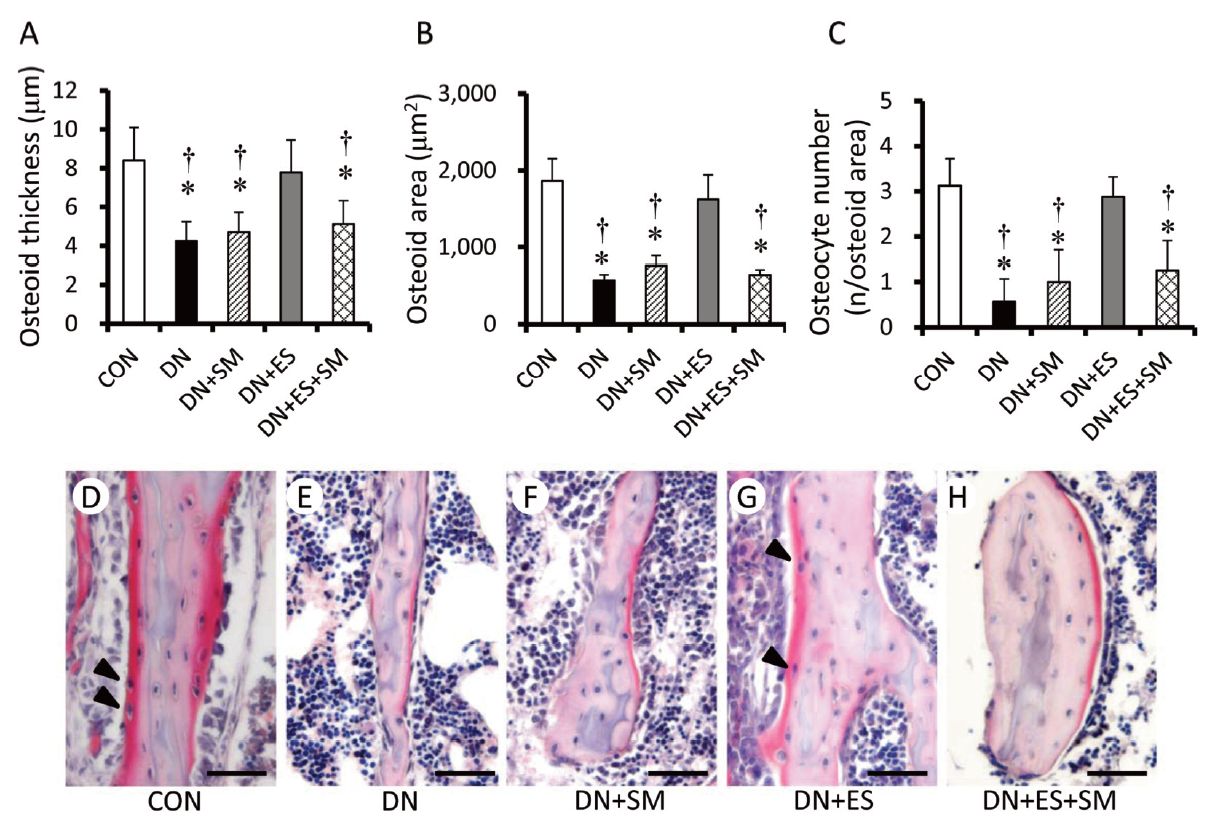

Tamaki H, Yotani K, Ogita F, Sugawara K, Kirimto H, Onishi H, Kasuga N, Yamamoto N. Effect of electrical stimulation-induced muscle force and streptomycin treatment on muscle and trabecular bone mass in early-stage disuse musculoskeletal atrophy. J Musculoskelet Neuronal Interact. 2015 Sep;15(3):270-8.